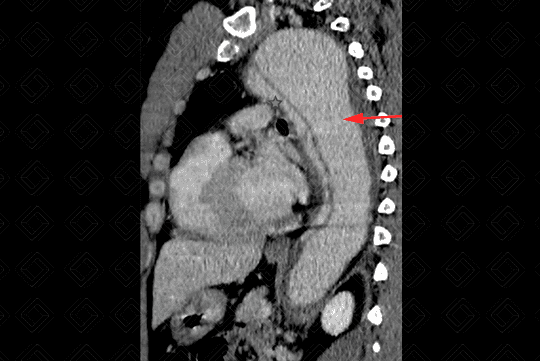

Descrição das imagens: Extensa dissecção da aorta descendente com dilatação da luz falsa (setas vermelhas) e redução das dimensões da luz verdadeira (asteriscos). É importante detalhar o suprimento dos ramos aórticos, ou seja, se estão sendo supridas pela falsa ou verdadeira luz. Neste paciente, observamos que a artéria renal esquerda (seta branca) está sendo suprida pela falsa luz (seta vermelha).

• Figura 1: Localizar a dissecção: as dissecções que envolvem aorta ascendente são tratadas cirurgicamente a fim de evitar complicações fatais, como: extensão para artérias coronárias, valva aórtica, pleura ou pericárdio. Já o acometimento somente da aorta descendente, em geral, possui manejo conservador;